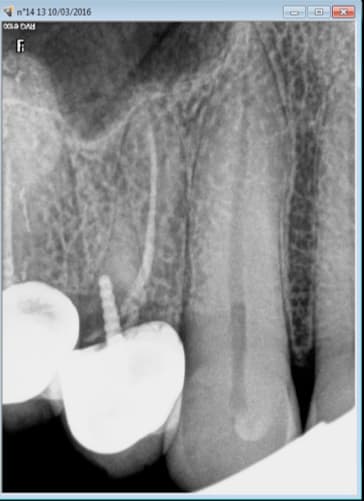

10/03/2016 à 20h16

Rassures toi meme si tu fais les pires bouses les patients ne s'en rendront pas compte avant des années et ne feront meme pas le rapprochement de la cause à effet. -)

Tu vois meme en cas de controle le CDC ne se pose meme pas la question du praticien qui est à l'origine de ce chef d'oeuvre.

Le patient n'a pas voulu que j'intervienne, la confiance ca se gagne.....

Il retiendra la leçon un de ces 4. -)

Tu peux te détendre. -)

Et c'est loin d'etre un cas isolé, celui là commence à ressentir une légère gène sur cette 14 traitée depuis des années. -)

Des exemples comme ca il y en a à l'infini. Ils devraient imposer des tarifs gratuits pour les endos, ca augmenterait encore plus la qualité. -)